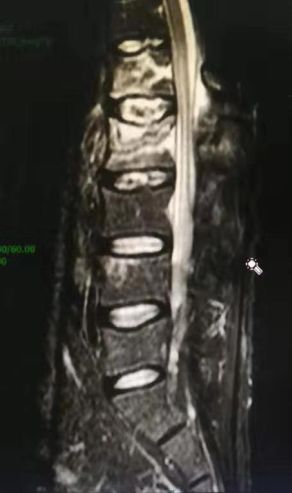

深圳市中医院骨三科的何升华主任经过仔细的检查、看片以后得出诊断结论:病人为强直性脊柱炎合并L1、L2椎体爆裂骨折。

腰椎MRI及CT显示腰1 腰2椎体新鲜压缩骨折

深圳市中医院骨三科的何主任考虑到患者年轻并且合并强直性脊柱炎,椎体多发硬化,不宜采取传统开放性手术。